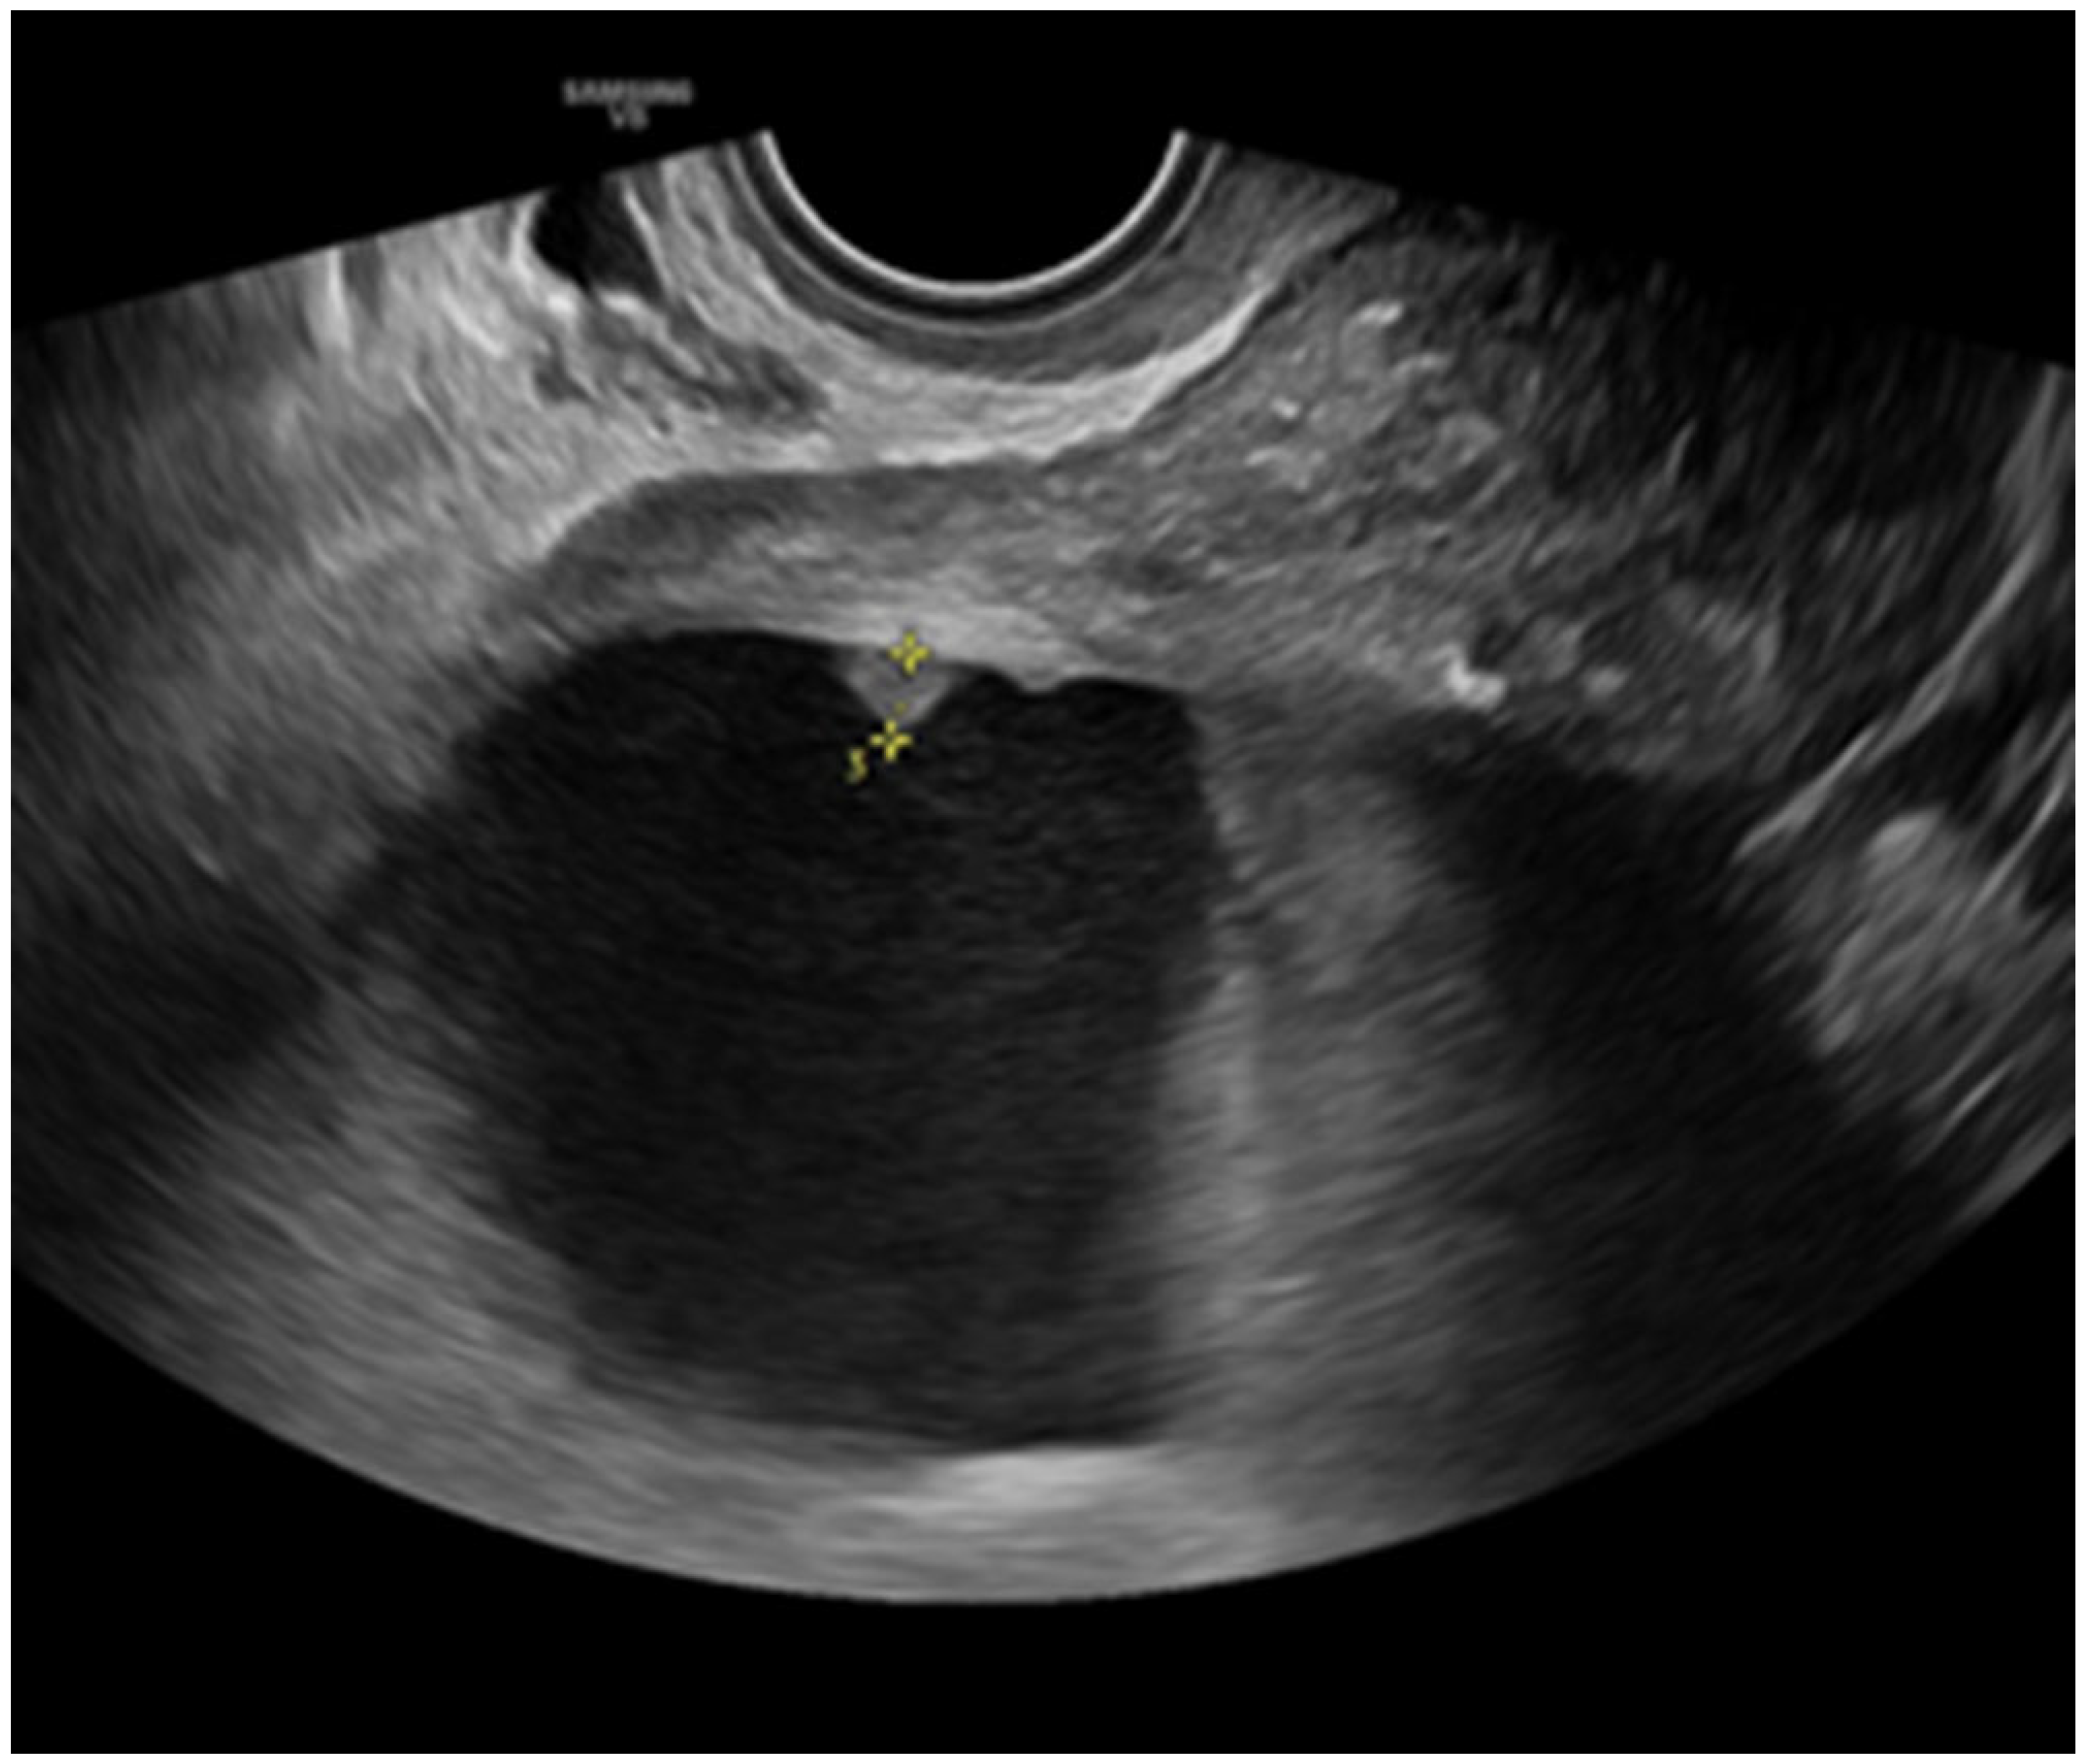

- Savelli, L.; De Iaco, P.; Ceccaroni, M.; Ghi, T.; Ceccarini, M.; Seracchioli, R.; Cacciatore, B. Transvaginal sonographic features of peritoneal carcinomatosis. Ultrasound Obstet. Gynecol. 2005, 26, 552–557. [Google Scholar] [CrossRef]

- Weinberger, V.; Fischerova, D.; Semeradova, I.; Slama, J.; Dundr, P.; Dusek, L.; Cibula, D.; Zikan, M. Prospective Evaluation of Ultrasound Accuracy in the Detection of Pelvic Carcinomatosis in Patients with Ovarian Cancer. Ultrasound Med. Biol. 2016, 42, 2196–2202. [Google Scholar] [CrossRef]

- Zikan, M.; Fischerova, D.; Semeradova, I.; Slama, J.; Dundr, P.; Weinberger, V.; Dusek, L.; Cibula, D. Accuracy of ultrasound in prediction of rectosigmoid infiltration in epithelial ovarian cancer. Ultrasound Obstet. Gynecol. 2017, 50, 533–538. [Google Scholar] [CrossRef]

- Fischerova, D. Ultrasound scanning of the pelvis and abdomen for staging of gynecological tumors: A review. Ultrasound Obstet. Gynecol. 2011, 38, 246–266. [Google Scholar] [CrossRef]